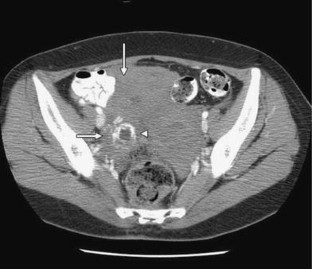

We present a case of a 37-year-old woman who presented with acute right lower quadrant abdominal pain. Work up with contrast enhanced CT to rule out appendicitis revealed dramatic ring enhancing cystic structure in the right adnexa corresponding to tubal ring sign of ectopic pregnancy seen on subsequent pelvic ultrasound. Right tubal ectopic pregnancy was confirmed at surgery.

Fig. 1.